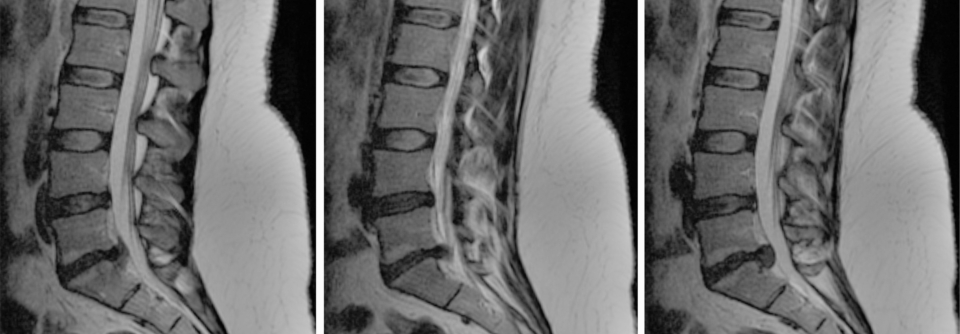

Lumbale degenerative Spondylolisthesis

Schrauben und Platten offenbar unnötig

Lassen sich Schmerzen in Bein und Rücken bei einer lumbalen degenerativen Spondylolisthesis durch die konservative Therapie nicht ausreichend…

Orthopädie , Chirurgie